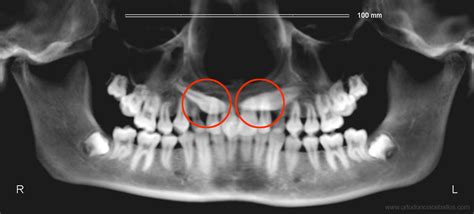

Diagnóstico

La primera prueba es la ortopantomografía digital o la radiografía panorámica. Esta radiografía es excelente para darnos suficiente información para saber la posición del canino.

Generalmente a los 8 o 9 años se puede palpar la prominencia de la corona del canino en la zona alta de la encía (en el fondo del vestíbulo). Un signo de mayor fiabilidad, detectable precozmente en radiografías panorámicas de individuos con sospecha de impactación del canino maxilar, es el grado del incisivo lateral adyacente.

Los autores Ericson y Kurol (1986) encontraron que un 91% de los caninos superiores permanentes que tenían una erupción con dirección incorrecta corregían su posición al extraer el temporal antes de los 11 años.